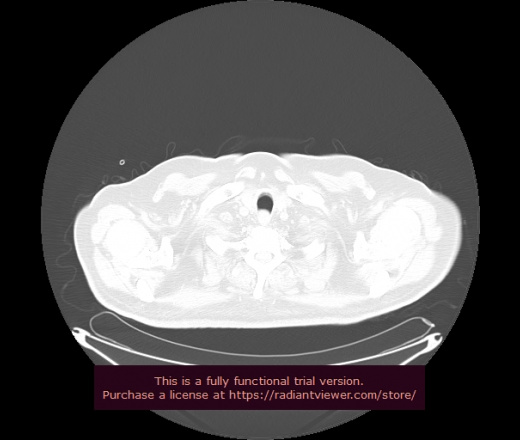

Уважаемые коллеги, если имеется интерес, сможете ли Вы спрогнозировать дальнейшее +-одинаковое течение процесса у 4 данных разных пациентов? Зацепиться где-то можно очень просто, где-то нельзя.